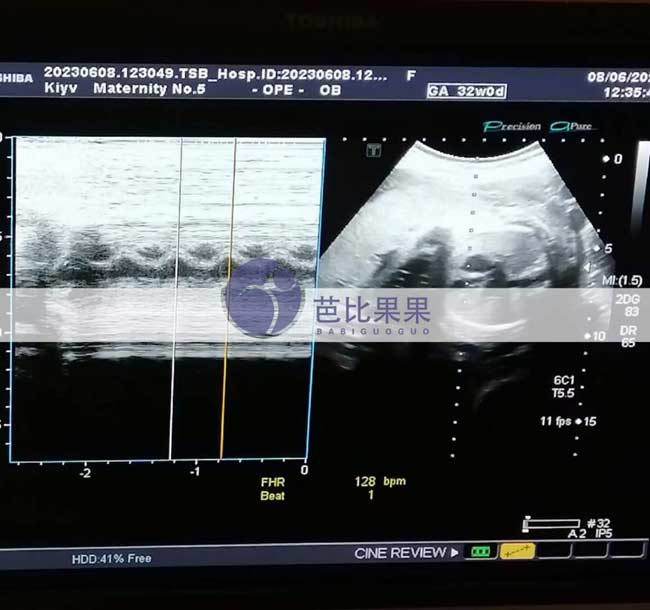

无锡W女士的乌克兰试管妈妈到妇产医院做32周的B超检查

无锡W女士的乌克兰试管妈妈到妇产医院做32周的B超检查,宝宝已经长得蛮大,离预产期越来越近,期待他的到来~